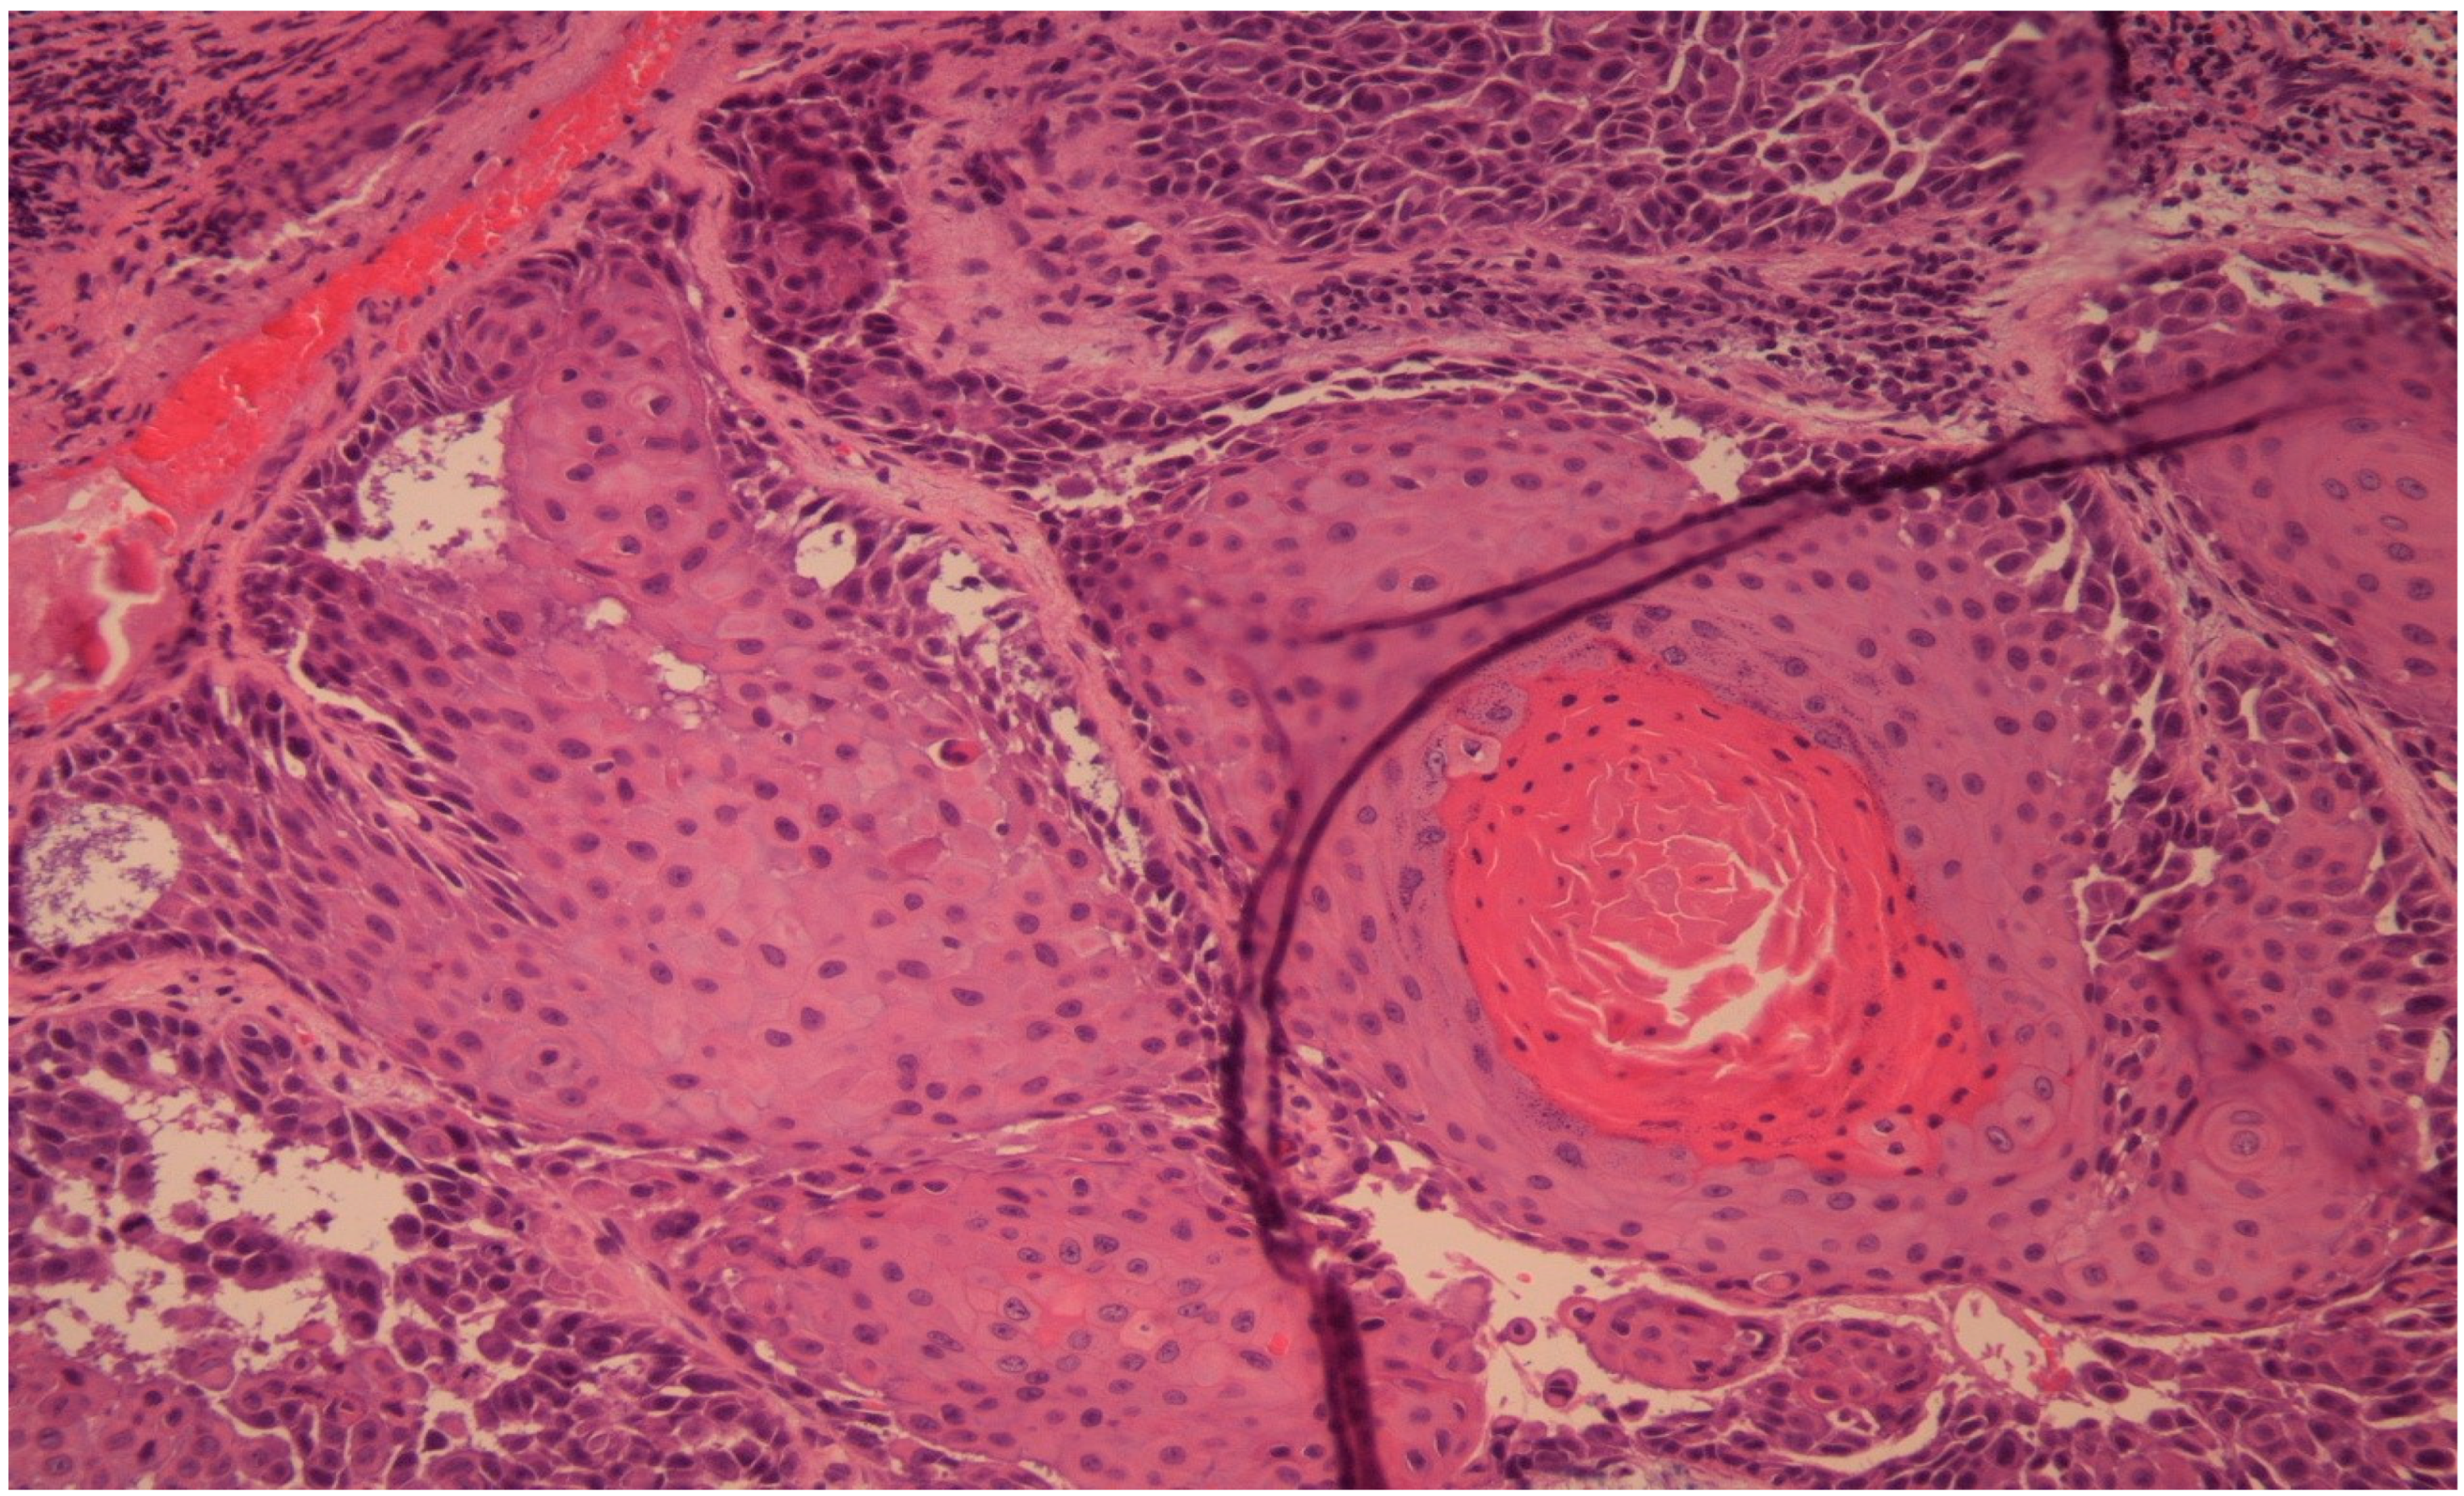

Figure 5. Hematoxylin and eosin staining, original magnification ×40. The histology result confirms SCC with focal acantholytic aspects and hyperkeratosis.

In order to obtain the histological diagnosis, an endonasal biopsy was performed, which resulted in sinonasal squamous cell carcinoma.

After the CT was performed, it revealed a volume-occupying lesion in the left maxillary sinus with perineural spread and invasion in the orbit, other sinuses and medial cranial fossa. Sinusitis does not have invasive characteristics, so it was excluded as a diagnostic option. In such cases an endonasal biopsy is the key point to the diagnosis. In our case, the histological result was classified as squamous cell carcinoma G1 (Figure 2).

Endonasal endoscopic biopsy was performed. The histology resulted in squamous cell carcinoma G1.